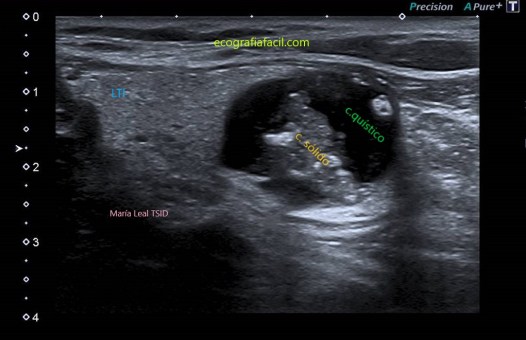

SÓLIDO QUÍSTICO:

Nódulo sólido-quístico